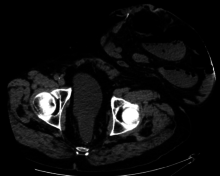

- Urostomy (also see Ileal conduit urinary diversion)